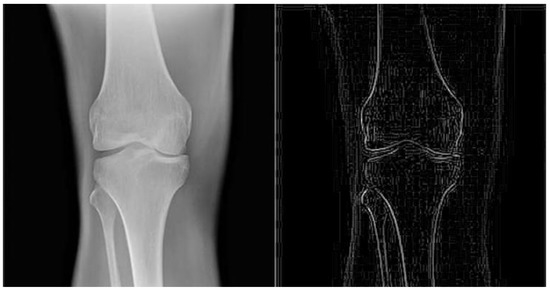

4.2. Knee Related Diagnosis